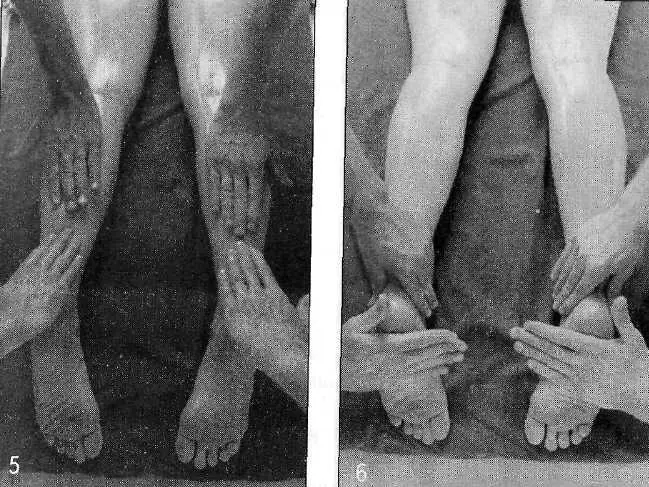

Бахья снехана представляет собой последовательность массажных движений, выполняемых в следующих направлениях: от пупка к голове, от головы к пупку, от пупка к ногам и от ног к пупку — на передней и задней поверхностях тела. Давление, прилагаемое массажистом, различается в зависимости от массируемой области (присутствия точек мармы). Согласно аюрведе, в точках мармы происходит соединение между физической материей тела и его внутренней мудростью. Стимуляция мармы оживляет и координирует взаимодействие субдош ваты, а следовательно, гармонизирует все нейрофизиологические процессы в организме.

Давление при массаже также увеличивает количество теплого кунжутного масла, проникающего в поры кожи. Обычно мы не думаем о коже как о поглощающем органе, хотя она может впитать действительно большое количество масла. Так же как и в других процедурах панчакармы, травяные масла выбираются с учетом конституции пациента.

В бахья снехане в основном используются три вида масел, каждое — для конкретной доши. Это вата шамак — для успокоения ваты, чанданбала — для успокоения питты и маханарайяна — для успокоения капхи. Каждое масло содержит травы, которые предписываются для успокоения соответствующих дош главным аюрведическим текстом «Чарака Самхита».

Массаж и травы позволяют маслу проникать глубоко в ткани и разрыхлять «укладку» амы в этих тканях, в том числе на стенках шрот. Помимо этого, снехана увеличивает гибкость тела, увеличивает силу, уменьшает стресс и питает ткани. Слово «снехана» буквально означает «доброта, нежность, любовь», и эта приятная процедура оправдывает свое название.